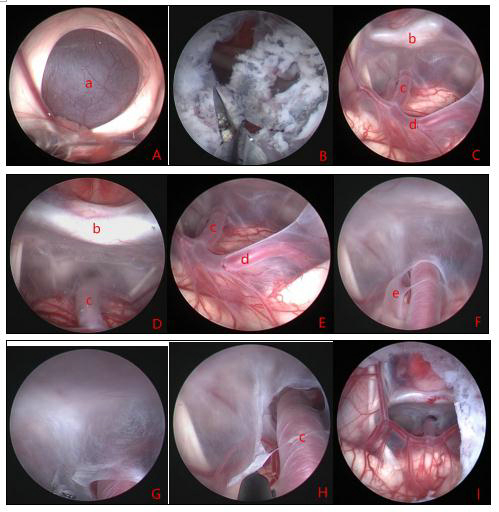

Figure 8. shows the intraoperative view of a suprasellar cyst with hydrocephalus. a: top of the suprasellar cyst; b: top fistula of the cyst; c, d, e: entry into the cyst through the top fistula, with the anatomy of the cyst's interior visible; f: fissure flap next to the basilar artery at the base of the cyst; g, h: fistula of the bottom wall of the cyst; i: bottom fistula completed, with the fistula above and below viewed from the lateral ventricle. a: cyst wall b: dorsal saddle c: basilar artery d: posterior cerebral artery e: fissure flap